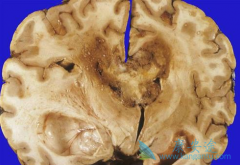

阿瓦斯汀( 贝伐单抗 )是治疗进展期胶质母细胞瘤(GBM)的重要手段之一,是在2009年被美国FDA批准治疗此病的药物。根据多项临床研究,阿瓦斯汀推荐的有效剂量为5mg/kg/周,并沿用至今。众所周知,过高的剂量可能会激活利于肿瘤生长的信号通路,并带来更 ...